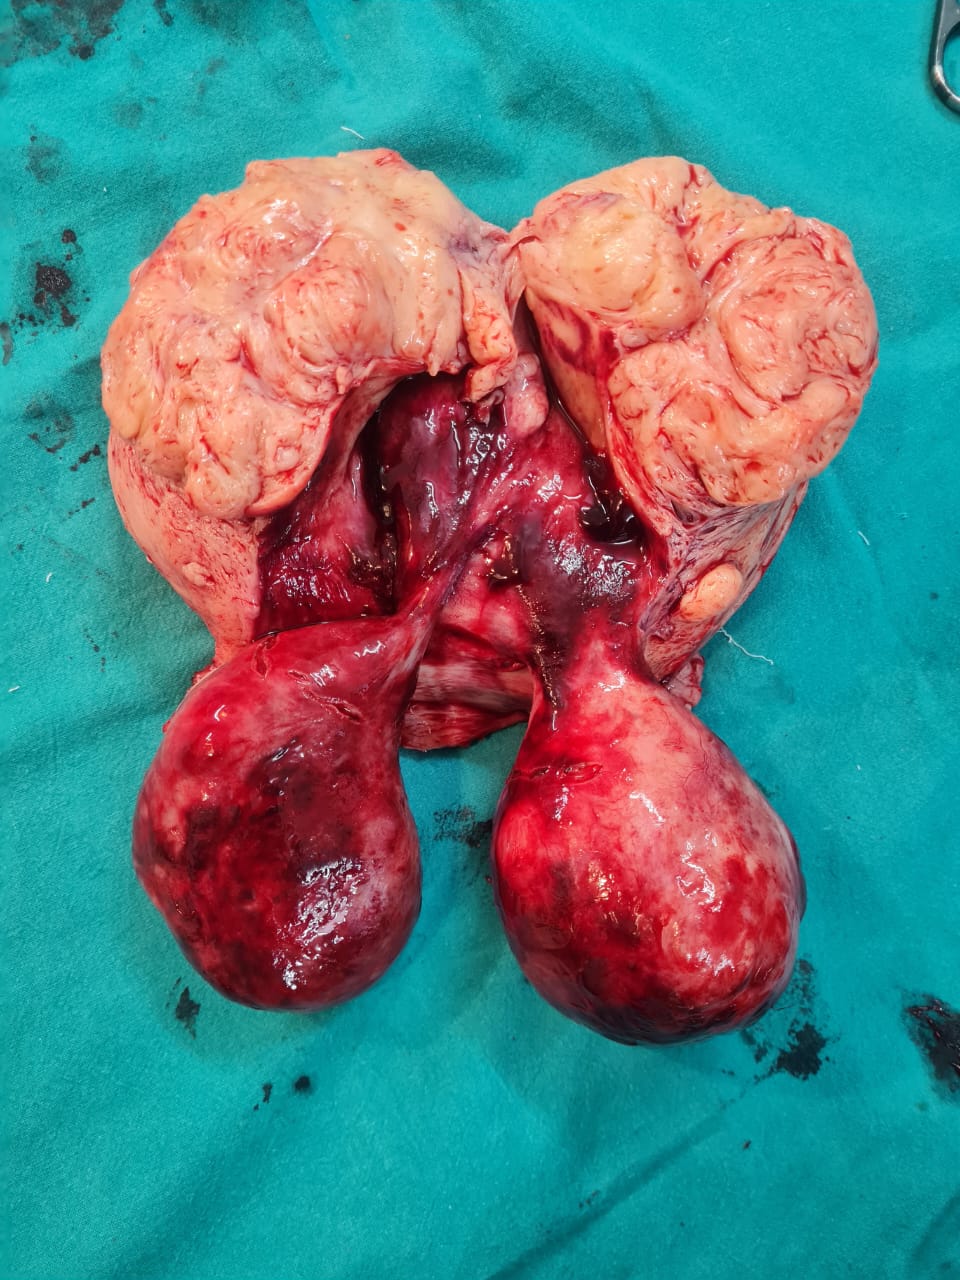

Proudly celebrating another triumph in gynecological excellence! Our expert surgical team just performed a total abdominal hysterectomy with bilateral salpingo-oophorectomy on a 50-year-old patient, flawlessly removing two massive 10×10 cm cervical fibroids and a large 9×7 cm posterior wall intramural fibroid. No complication.